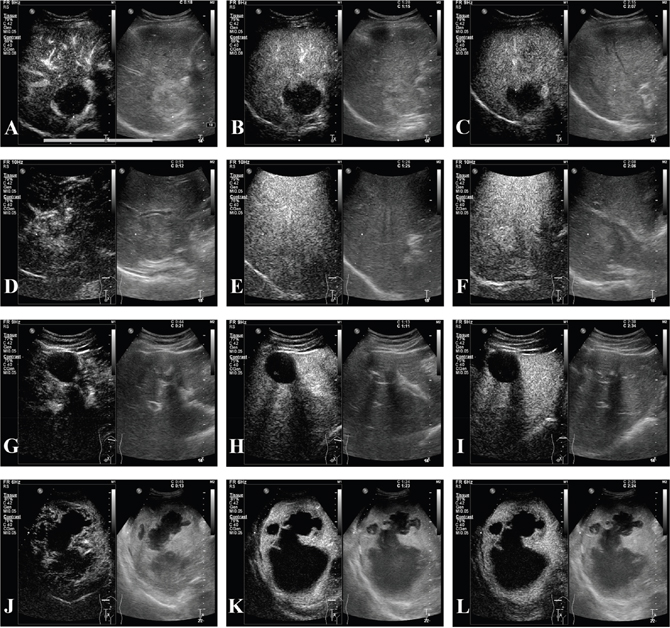

In conventional US (in Table 3), the constituent ratio of the baseline pattern differed between primary hepatic cancer and benign lesions (p < 0.001). Specifically, more primary liver cancers than benign lesions were hypoechoic (240/296, 81.1% vs. 11/32, 34.4%, p < 0.001), while benign lesions were likely to be hyperechoic (14/32, 43.8% vs.12/296, 4.1%, p < 0.001). Hepatic malignant tumors and benign lesions displayed different enhancement patterns in every phase: the arterial phase (p = 0.009), the portal phase (p < 0.001) and the delayed phase (p < 0.001). In the arterial phase, the primary differences related to the homogeneous and partial hyperenhancement of malignant tumors and benign lesions, 188/296, 63.5% vs. 13/32, 40.6% and p = 0.012; 64/296, 21.6% vs. 15/32, 46.9% and p = 0.002, respectively. In the portal and delayed phases, benign nodules still showed hyperenhancement 15/32, 46.9% vs. 0/296, 0.0% (p < 0.001); in the delayed phase, the rates were 14/32, 43.7% vs. 0/296, 0.0% (p < 0.001), but the benign nodules showed a much lower rate of isoenhancement and hypoenhancement than the malignant tumors (in the portal phase: 17/32, 53.2% vs. 296/296, 100% and p < 0.001; in the delayed phase: 18/32, 56.3% vs. 296/296 100% and p < 0.001). CEUS images for benign hepatic lesions were showed in Figure 1.

Figure 1: CEUS of hepatic benign lesions. (A-C) A 46-year-old female patient with pathologically proven hemangioma which was 4.8cm in the right lobe and thrombosis inside the lesion; (A) peripheral hyperenhancement in arterial phase; (B-C) hyperenhancement in portal and delayed phases, and irregular patchy nonenhancement area inside the tumor was seen in all phases; (D-F) a 29-year-old male patient with pathologically confirmed focal nodular hyperplasia (FNH) which was 5.0cm in the right lobe; (D) hyperenhancement from the core to periphery in arterial phase; (E-F) peripheral hyperenhancement in portal and delayed phases, and central area presenting hypoenhancement; (G-I) a 35-year-old male patient with pathologically confirmed hepatic echinococcosis which was 4.4cm in the left lobe and nonenhancement in central area. (J-L) a 51-year-old male patient with pathogen test of drainage; (J) peripheral hyperenhancement in arterial phase; (K-L) isoenhancement to hypoenhancement in portal and delayed phases.